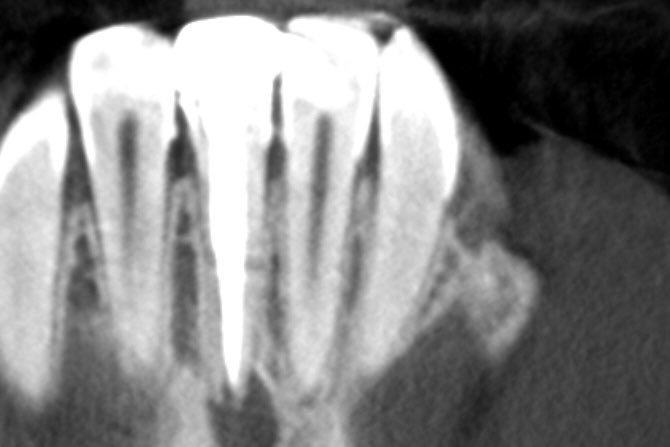

طبيب مقيم في علاج الجذور و عصب الأسنان 🦷 🦷 Endodontic resident at @ksmcmedia 📍Riyadh